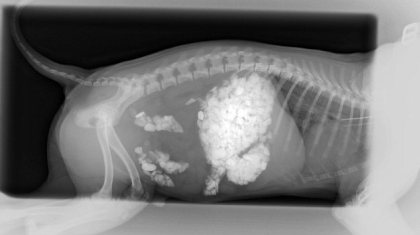

Περήφανη πρέπει να είναι η ιδιοκτήτρια του Άλφι για την εξυπνάδα του, καθώς ο συμπαθέστατος – κατά τα άλλα – σκύλος έφαγε 2,5 κιλά πέτρες!

Το περίεργο στην όλη υπόθεση είναι ότι ο σκύλος δε φάνηκε να δυσανασχετεί με τόσο βάρος στην κοιλιά του και η ιδιοκτήτριά του κατάλαβε ό τι κάτι τρέχει μόνο όταν τον πήρε αγκαλιά.